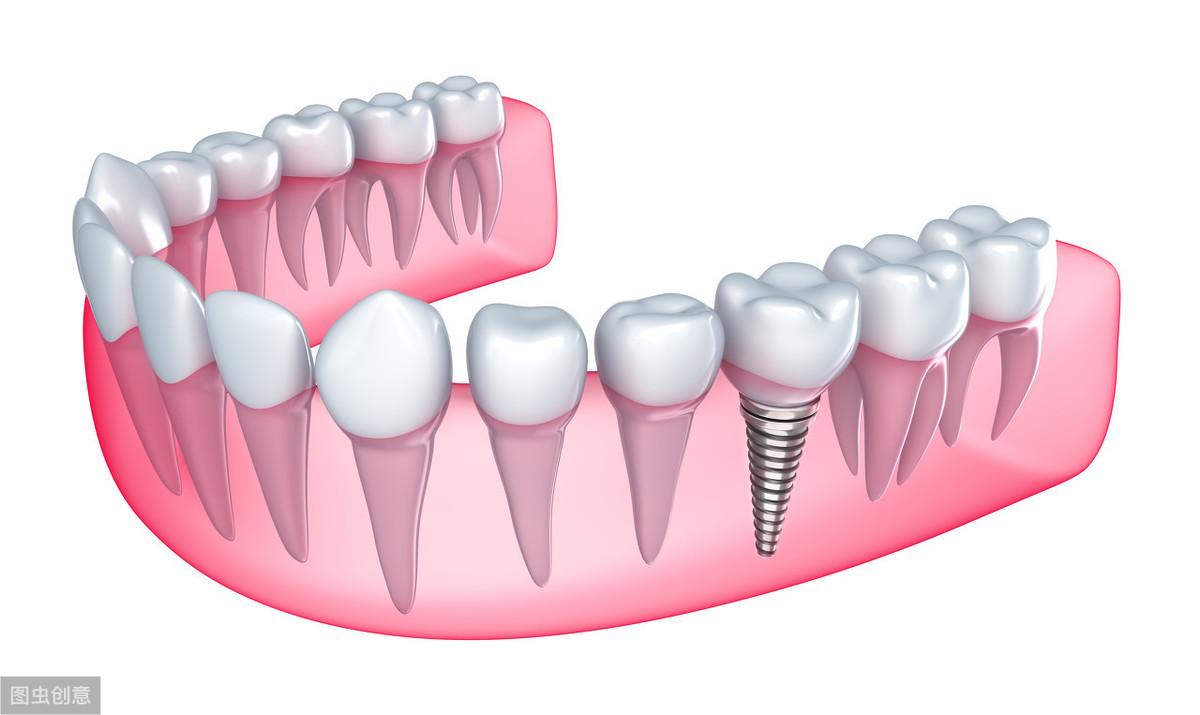

種植牙手術示意圖

種植牙技術是近幾十年出現(xiàn)在大眾視野中的一種修復缺失牙體的方法。一顆完整的種植牙體由三部分組成:種植體、基臺、人工牙冠。

手術過程就是將種植體植入患者的牙體缺失處,待其傷口愈合,種植體與牙槽骨結合牢固后,將基臺安裝在種植體上,再將人工牙冠安裝在基臺上,形成完整而堅固的人工牙體。